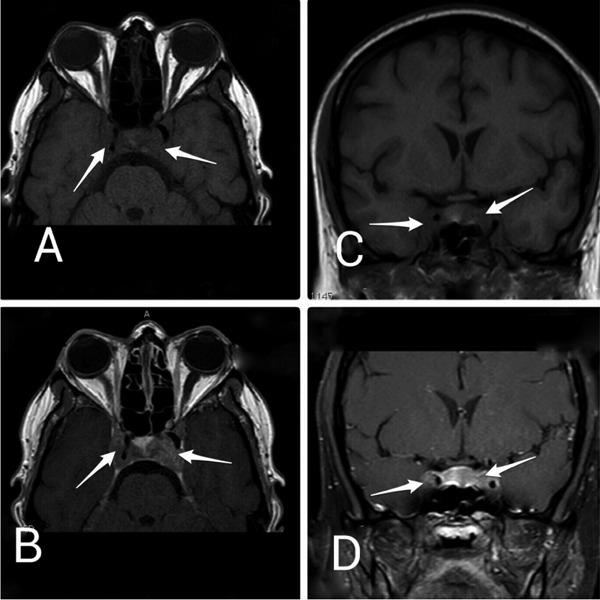

Cavernous sinus thrombosis (CST) is a rare condition that is usually associated with infections, pregnancy, vasculitis and some types of medication, such as the contraceptive pill and paraneoplastic. Primary Burkitt lymphoma (PBL) of the thyroid gland is very uncommon and the clinical description of such cases has been largely limited to case reports. In this paper, we present a case of CST as the first manifestation of PBL of the thyroid gland. To the best of our knowledge, our patient is the first case report of PBL of the thyroid gland that presents with bilateral CST.